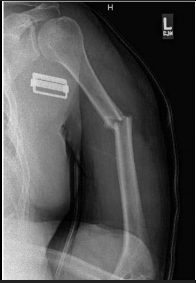

The nerve injured when this injury occurs.

What is a radial nerve injury?